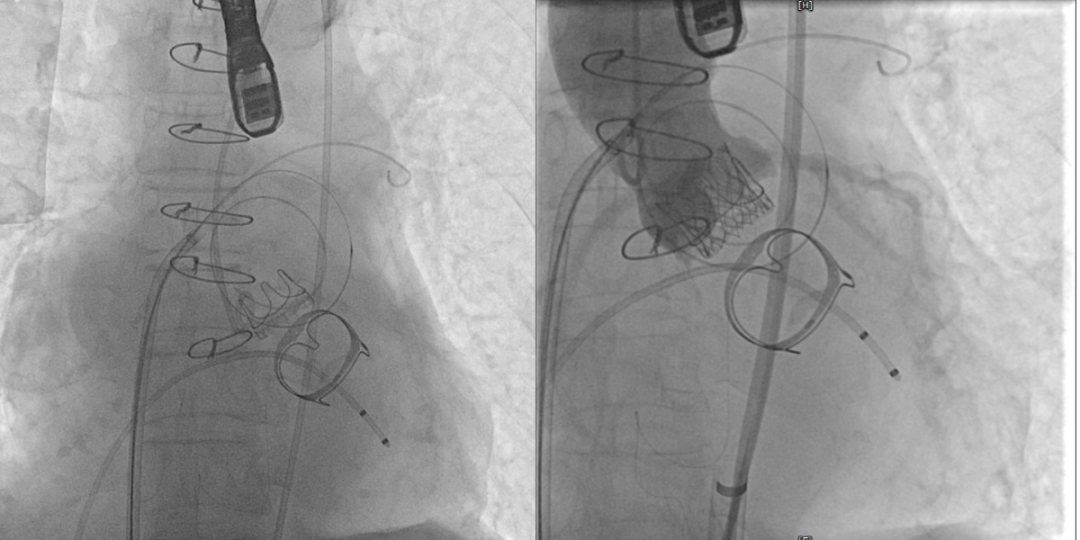

术前(图1)和TAVR 植入(图2)

TMVR 术后房间隔封堵